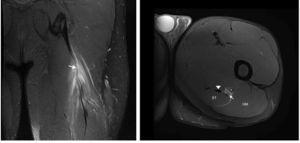

Figura 2 Les imatges coronal i axial en T2 amb supressió de greix de l’isquiotibial esquerre mostren canvis de gruix i intensitat del senyal del tendó lliure (fletxa), contorns borrosos i discontinuïtat ampliada fins a UMT proximal. Existeix retracció distal lleu d’UMT proximal. Ventre del múscul semitendinós (ST), gluti major (GM), tendó semimembranós (punta de fletxa) i nervi ciàtic (*).